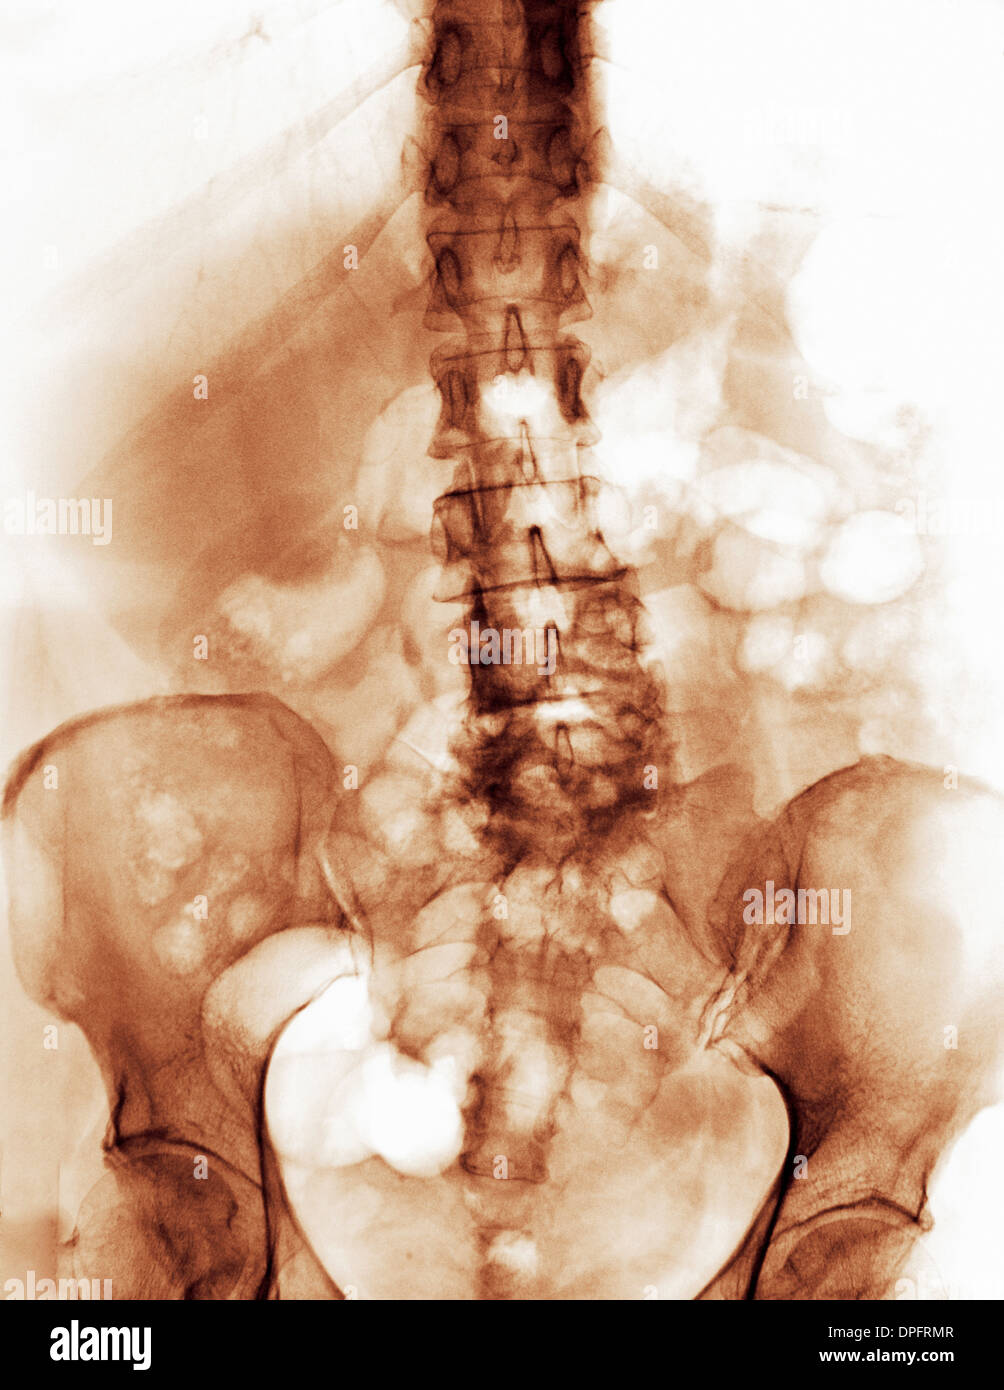

spine x-ray with degenerative arthritic changes Stock Photohttps://www.alamy.com/image-license-details/?v=1https://www.alamy.com/spine-x-ray-with-degenerative-arthritic-changes-image65501438.html

spine x-ray with degenerative arthritic changes Stock Photohttps://www.alamy.com/image-license-details/?v=1https://www.alamy.com/spine-x-ray-with-degenerative-arthritic-changes-image65501438.htmlRFDPFRN2–spine x-ray with degenerative arthritic changes

spine x-ray with degenerative arthritic changes Stock Photohttps://www.alamy.com/image-license-details/?v=1https://www.alamy.com/spine-x-ray-with-degenerative-arthritic-changes-image65501431.html

spine x-ray with degenerative arthritic changes Stock Photohttps://www.alamy.com/image-license-details/?v=1https://www.alamy.com/spine-x-ray-with-degenerative-arthritic-changes-image65501431.htmlRFDPFRMR–spine x-ray with degenerative arthritic changes